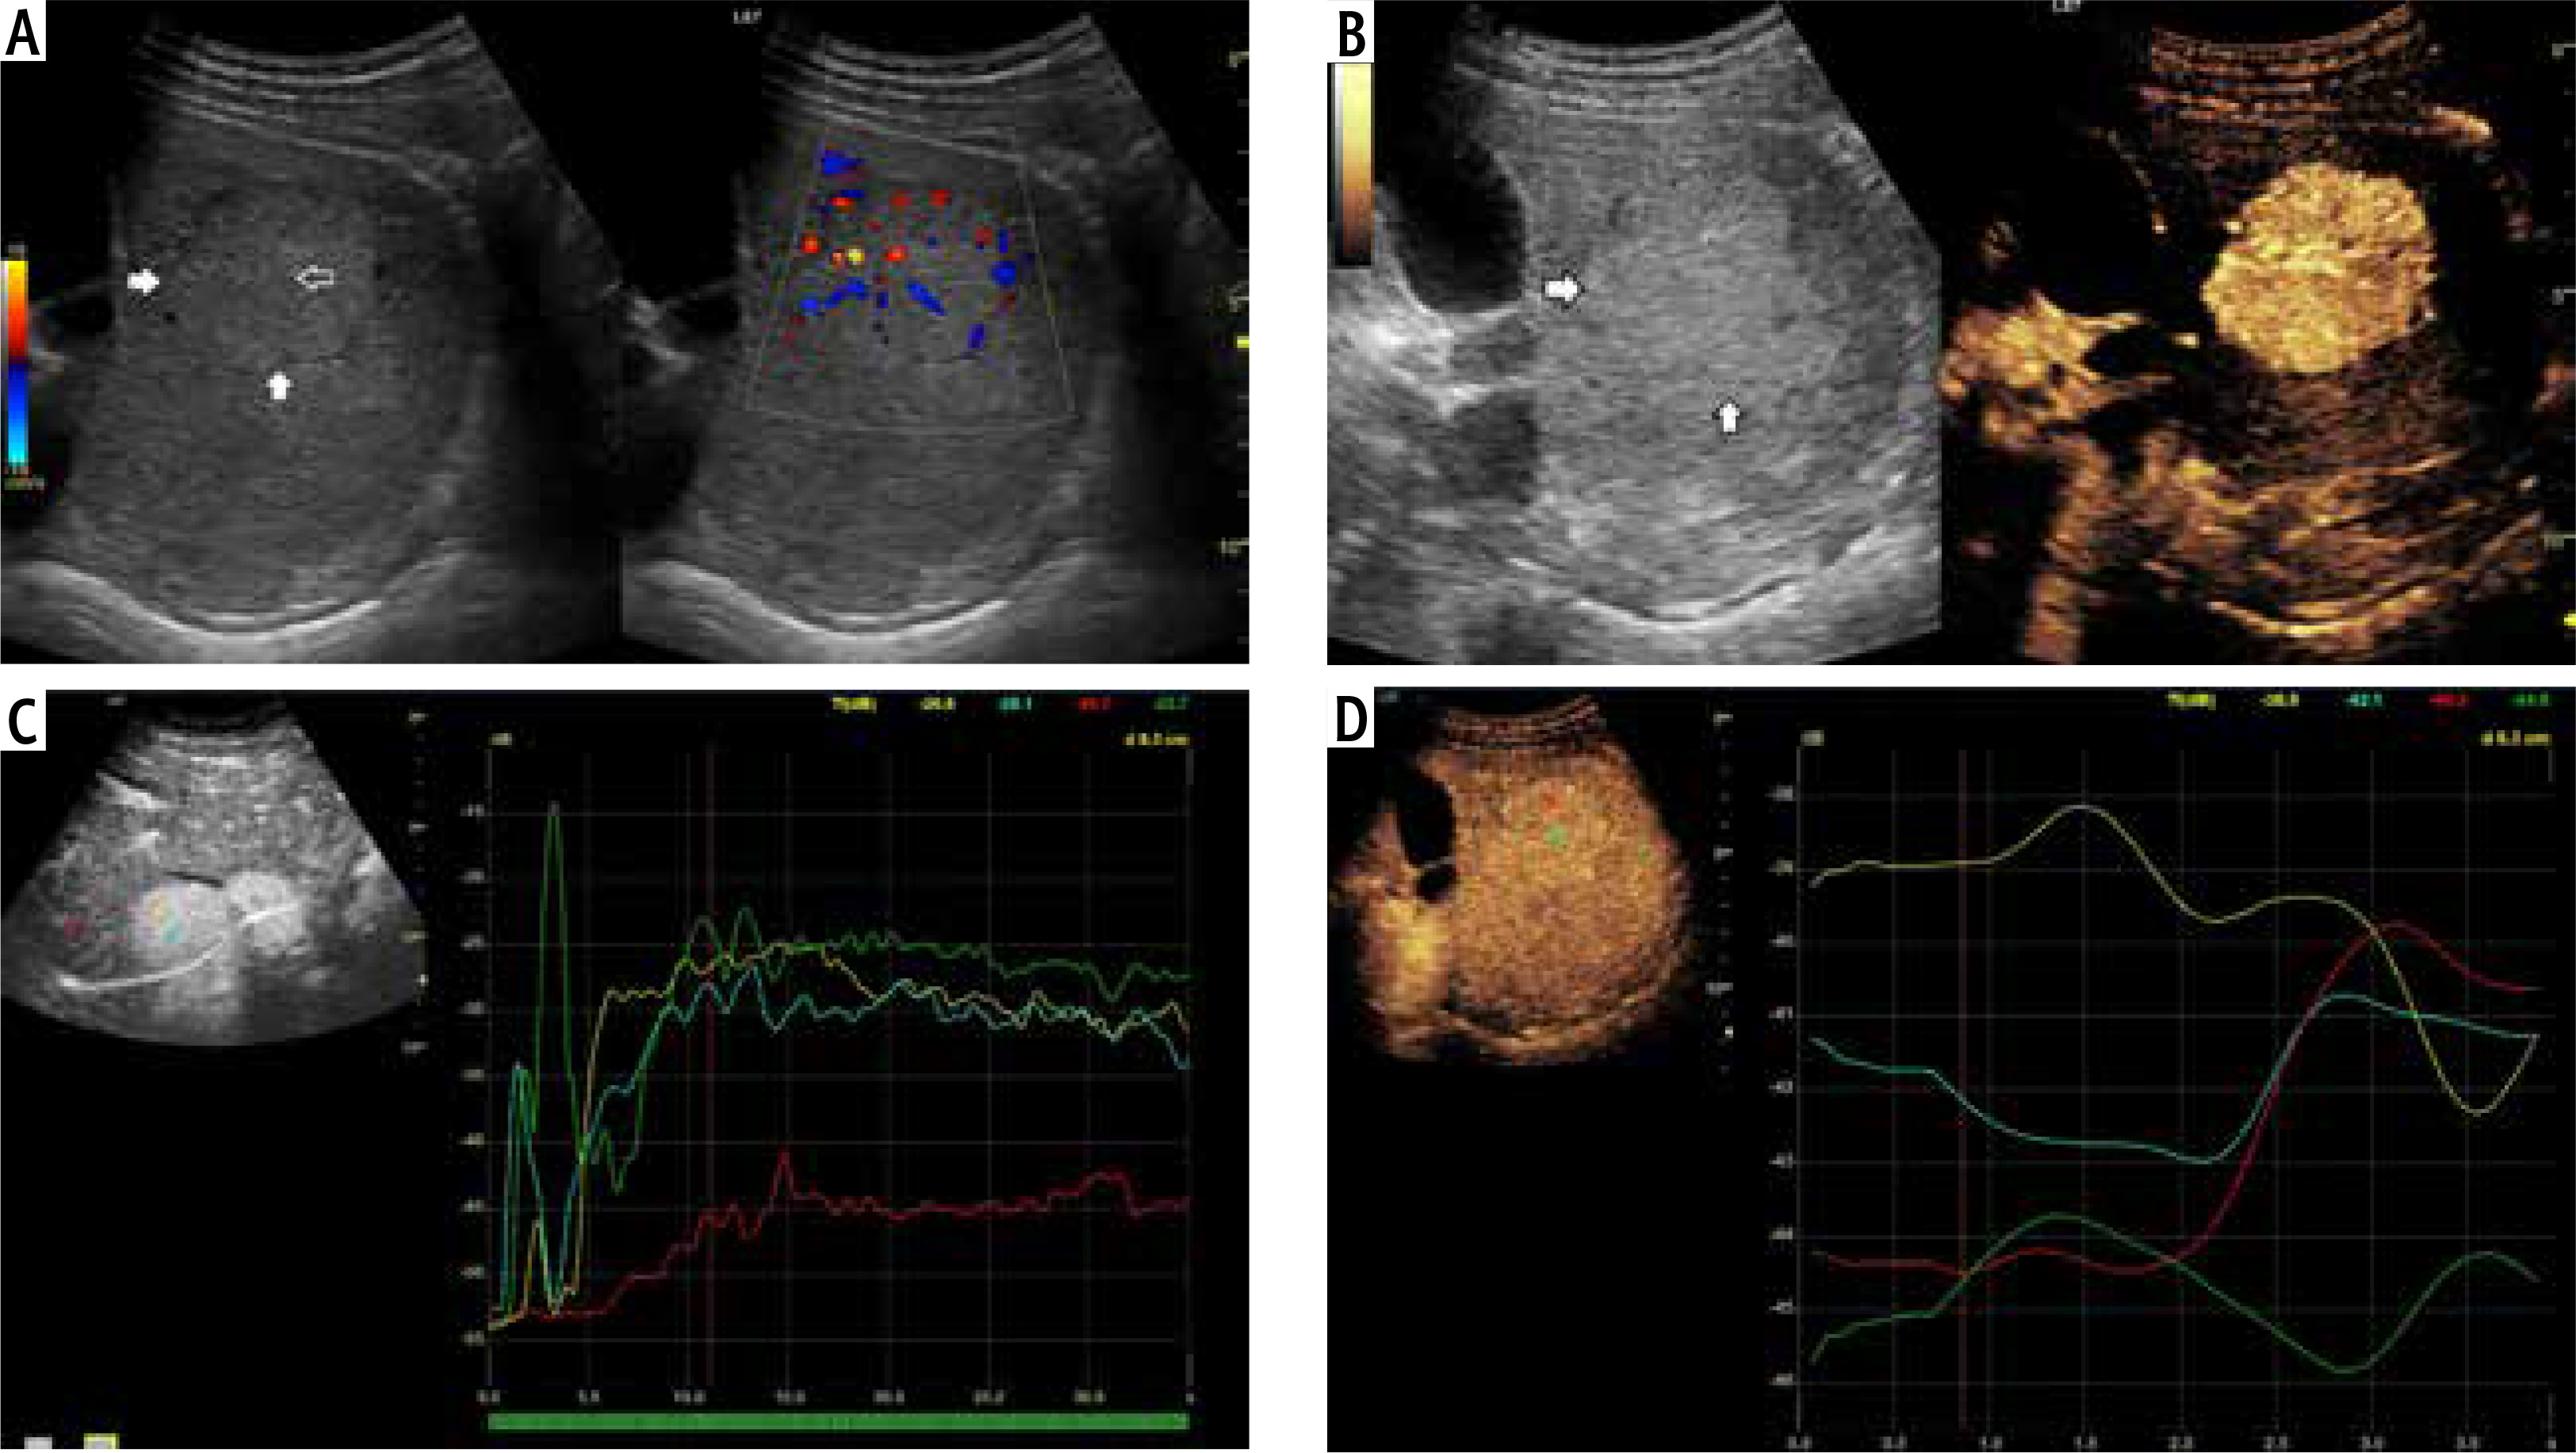

Fig. 5

A) Image of ultrasound and color Doppler in the transverse plane, focal lesion in the right lobe of the liver identified in MRI as HCA (full white arrows). Echogenicity of the lesion is slightly higher in relation to the liver parenchyma. B) Image of CEUS in the transverse plane of the lesion identified in MRI as HCA (full white arrows). Enhancement in the early phase is higher in relation to the liver parenchyma. C) Image of CEUS. Curves of enhancement in early phase of examination. The tumor area – yellow and blue lines, enhancement appears in the hepatic veins with slight delay – the green line. Weaker and delayed enhancements in the liver parenchyma – the red line. Disturbance of the curves in the early phase of the study (0-5 s) is caused by displacement of the liver due to breathing. D) Image of CEUS. Curves of enhancement in the areas of interest in the late phase of the study are aligned. The tumor area – blue and yellow line, the hepatic vein is slightly more intensively enhanced – blue line. Slightly weaker enhancement of the liver parenchyma – the red line

Fig. 6

A) Image of ultrasound and color Doppler in the transverse plane, focal lesion in the right lobe of the liver identified in MRI as FNH (full white arrows). Echogenicity of the lesion is slightly higher in relation to the liver parenchyma. In the central part, a small scar (an empty white arrow) is more clearly visible in the color Doppler option. B) Image of CEUS in the transverse plane of the lesion identified in MR as FNH (full white arrows). Enhancement in the early phase is higher in relation to the liver parenchyma. In the central part, the area containing the vessels, corresponding to the central fibrous scar. C) Image of CEUS. Enhancement curves in the early phase of examination. The tumor area – yellow and blue lines, with slightly delayed enhancement appears in the portal system – red line. Weaker and delayed enhancement of the liver parenchyma – the green line. D) Image of CEUS. Curves of enhancement in late phase of examination align. Area of tumor – blue and red lines, slightly stronger enhancement portal vein – yellow line. Slightly weaker enhancement of the liver parenchyma – the green line